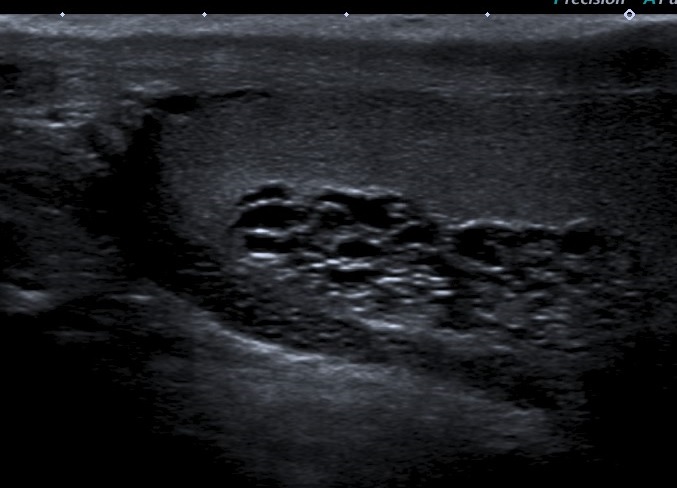

• Se realiza estudio con sonda lineal de alta frecuencia. Se explora el escroto y ambos testículos (figura 1), que presentan tamaño, morfología y ecoestructura normal, así como correcto flujo Doppler (figura 2). A nivel del teste izquierdo, se observa una colección de pequeñas imágenes anecoicas en el mediastino testicular, pseudotubulares. Además, una imagen anecoica, redondeada, quística, a nivel de la cabeza del epidídimo (figura 3).

• Se solicita ecografía testicular reglada que es informada como ectasia tubular de la rete testis en probable relación con antecedente de vasectomía y en la que se visualiza quiste de epidídimo izquierdo de 15 x 8 mm e hidrocele grado I, sin varicocele asociado.

• Juicio clínico: Quiste de epidídimo y ectasia tubular segmentaria de la rete testis.